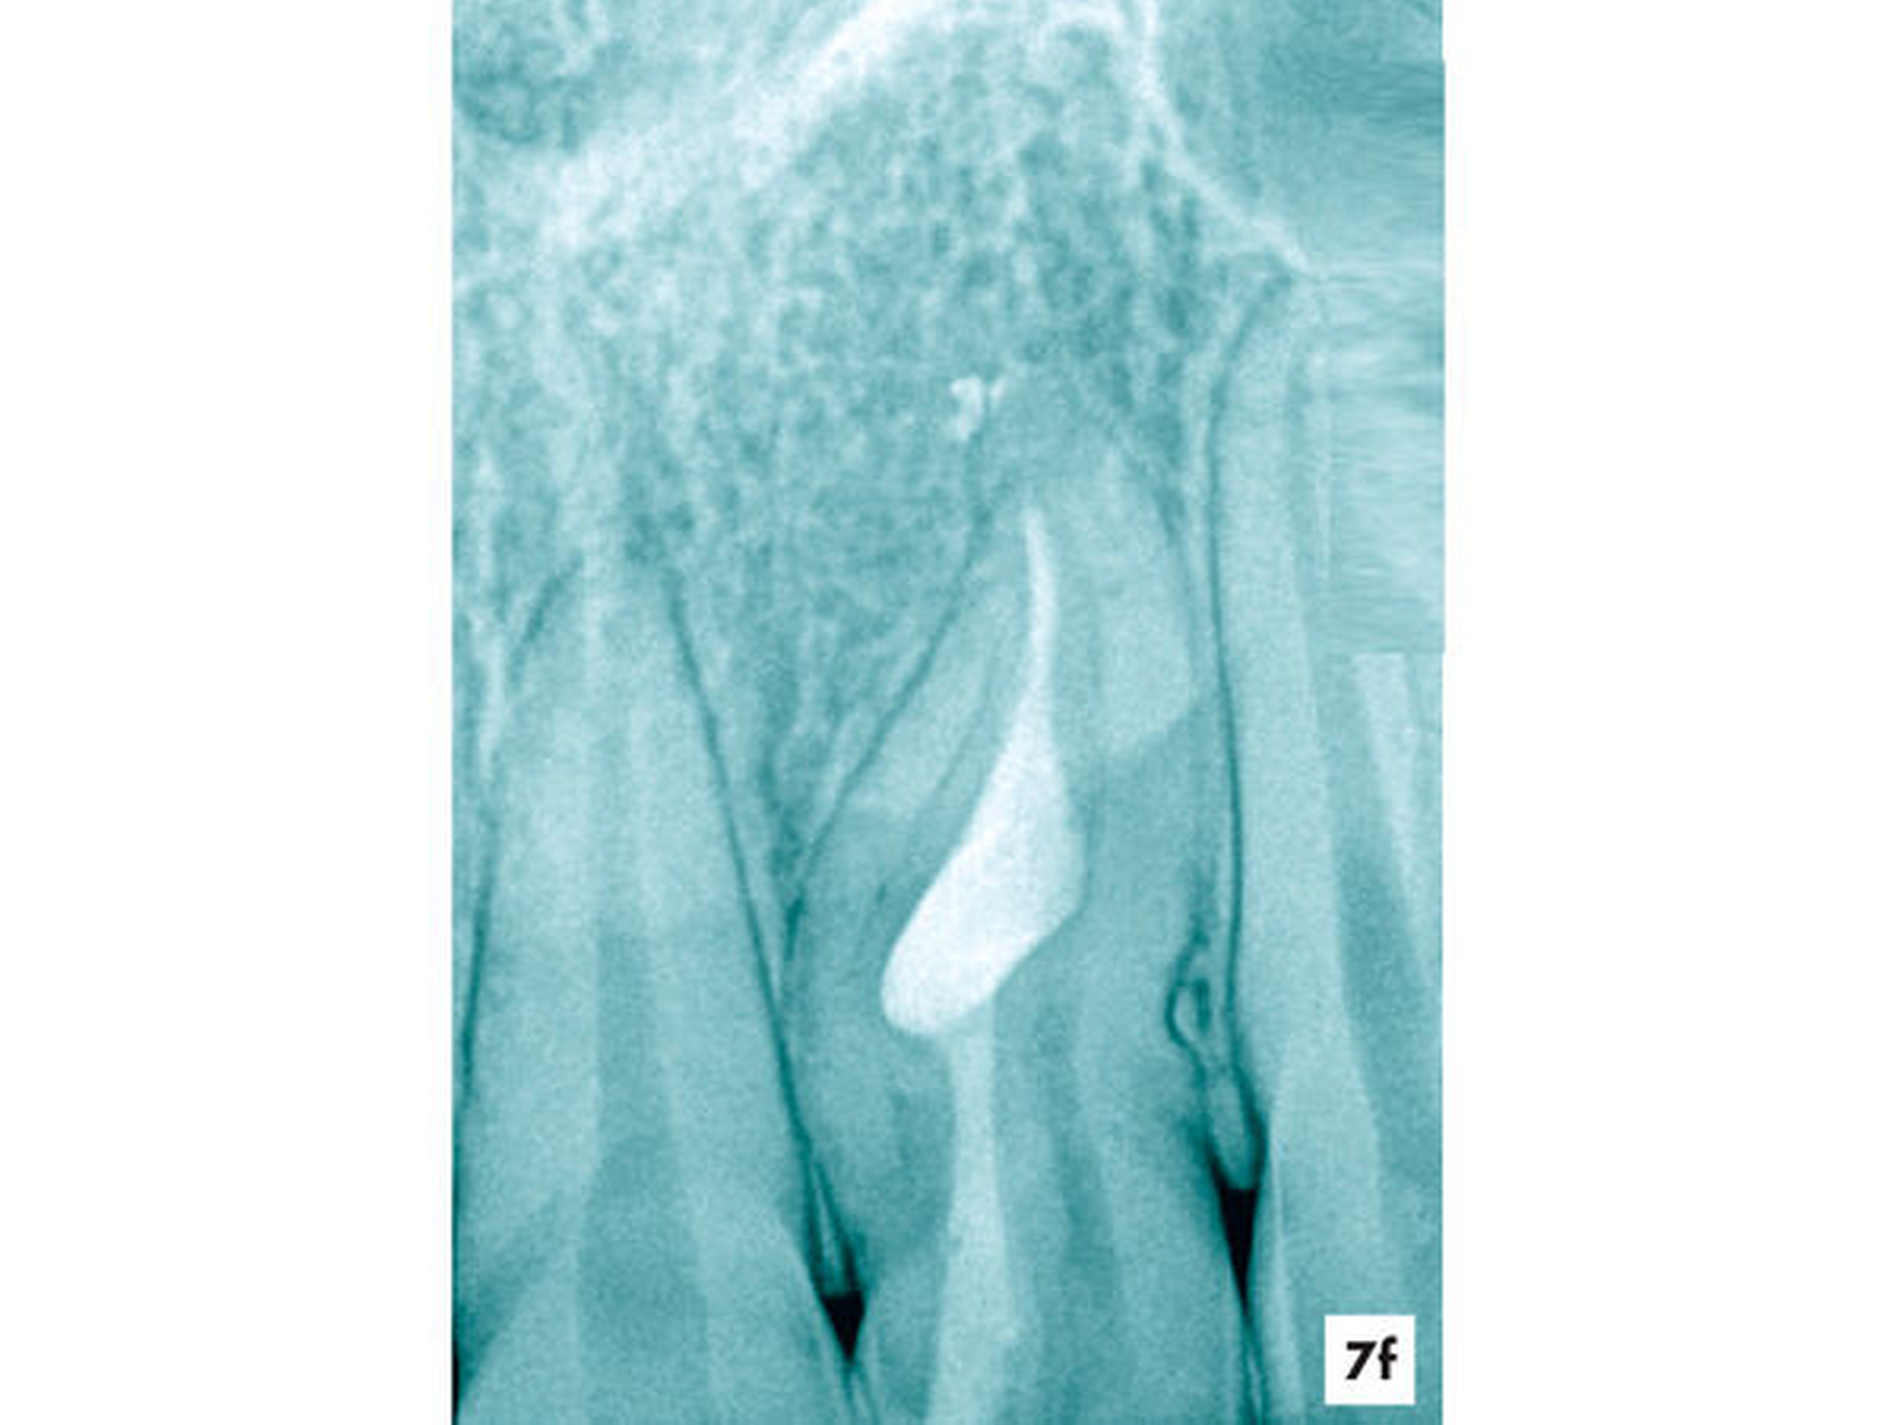

Unter Sicht mit dem Dentalmikroskop gelang es, den Zugang zur Invagination aufzufinden und minimalinvasiv zu erweitern (Abbildung 7b). Nach einer abschließenden Desinfektion konnte der Hohlraum vollständig mit Guttapercha und einem Epoxidharz-haltigen Sealer verschlossen werden, ohne die Vitalität des Zahnes zu beeinträchtigen. Fünf Jahre nach Abschluss der einzeitigen Wurzelkanalbehandlung reagierte der symptomlose Zahn positiv auf den Sensibilitätstest und die apikale Aufhellung erschien deutlich verkleinert (Abbildungen 7e und 7f).